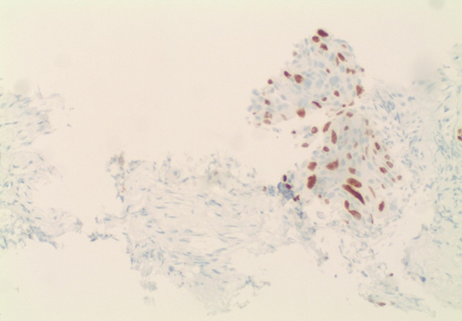

papillary thyroid carcinoma. Immunohistochemical staining was also performed and demonstrated TTF-1

and PAX-8 positivity; (Figure 2)

Figure 2. Immunohistochemical Stain,

TTF-1 Positivity